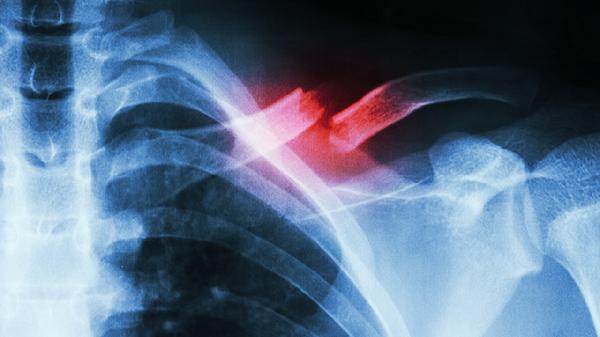

肋软骨炎可通过热敷、药物治疗、物理治疗、中医调理、手术治疗等方式改善。肋软骨炎可能与外伤、慢性劳损、感染等因素有关,通常表现为局部疼痛、肿胀等症状。

手术治疗适用于保守治疗无效、病情严重的肋软骨炎患者。手术方式包括肋软骨切除、病灶清除等,需根据具体情况选择。术后需注意伤口护理,避免感染。恢复期间应避免剧烈运动,定期复查评估恢复情况。手术治疗存在一定风险,需与医生充分沟通后决定。